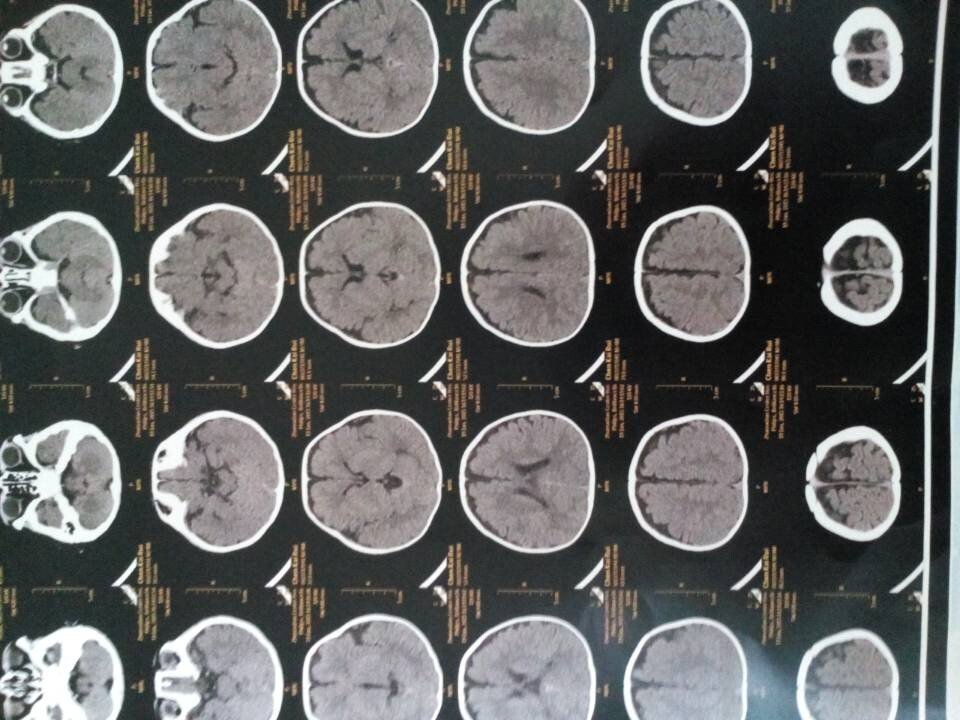

医生您好,宝宝5个月了,体检时候两腿粗细长短不一样,爱伸舌头,怎么回事,求帮助,希望给看一下 有拍ct,说是双下肢不等长 点击展开 匿名用户 2015-01-20 20:48 为您推荐: 其他回答 从ct情况看存在硬膜下腔积液情况的导致的上述情况的可能性的,这种情况需要到医院儿科看看,是不是脑损伤的情况导致的 知道张纪阳 2015-01-22 20:15 相关问题 宝宝俩月,爱伸舌头!怎么回事儿?谢谢 医生您好,我家宝宝三个半月,拉屎带有类似鼻涕似的黏液,经医院检查,是肠炎,医生给开的妈咪爱和头包地 有医生在吗?宝宝4个月了,老爱申舌头怎么回事?有宝妈知道的吗?